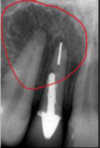

identify the anatomical structure below.

mandibular canal